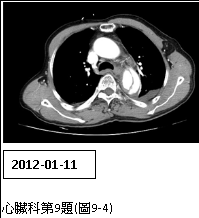

9. 男性病人,72歲,因尖銳性上背部疼痛突然發作,同時伴有急促呼吸及眩暈,乃往急診求治。時,血壓149/91 mmHg;心跳,70/min; RR, 20/min;其他理學檢查並無任何異常。病人每天抽煙一包,已有五十多年。Chest X-ray、ECG及CT,如圖9-1、圖9-2、圖9-3A及圖9-3B後,及其初步處置,後轉送加護病房途中,又突發後背疼,同時雙腳麻及疼痛,並呈現雙腳發紺,乃急照另次CT如圖9-4所示。請問下列何者決策不恰當? (A) 控制心收縮血壓在100-120 mmHg及心跳60-80/min (B) 靜脈注射Labetalol 30 mg/min (C) 口服Propranolol 20 mg tid po (D)口服Aspirin 100 mg qd 及Clopidogrel 75 mg qd (E) 外科會診,緊急手術